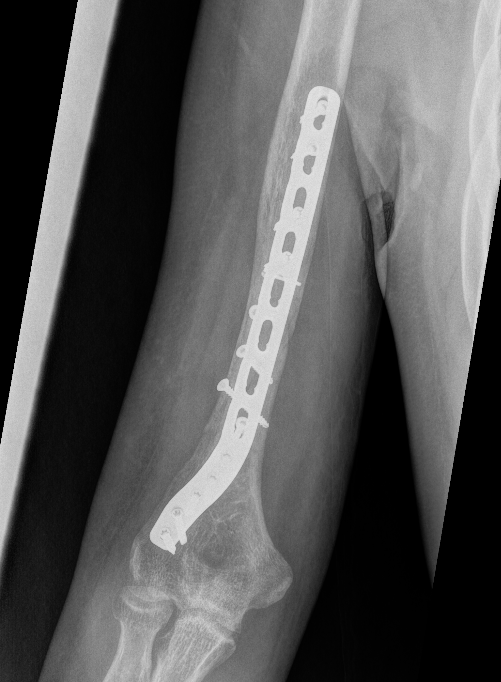

Humeral Fracture SegmentalHumeral Plate LateralHumeral Plate Long AP

Segmental fracture ORIF